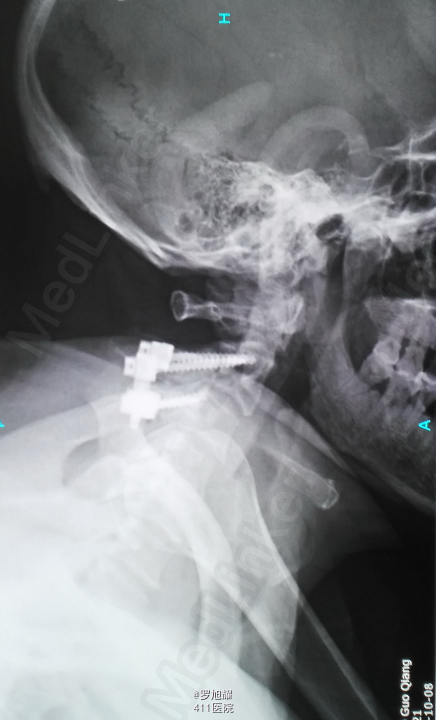

入院立即给与大剂量甲强龙冲击治疗,辅以甘露醇脱水消肿,兰索拉唑保护胃黏膜,腺苷钴胺恩经复营养神经,伤后10天复查MRI脊髓信号增高明显,两周后生命体征稳定,肢体感觉和肌力见部分恢复,行颈2椎弓根螺钉、颈3侧块钉内固定术,因神经压迫不明显未行椎板切除减压。 术后3月骨折线基本消失,患者感觉肌力几乎完全正常,右肩残留疼痛磁共振检查发现肩袖损伤,暂予局封治疗症状缓解。